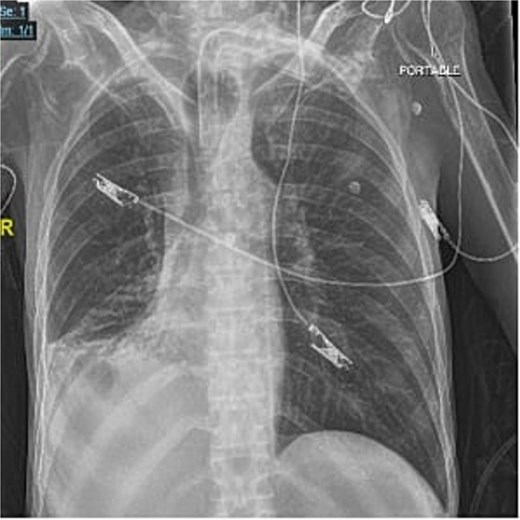

A 40-year-old male who is known to have amyotrophic lateral sclerosis was admitted to the intensive care unit for ventilatory support. He underwent surgical tracheostomy for long-term mechanical ventilation dependence, a double-lumen tracheostomy tube with an internal diameter of 8 mm and a maximum cuff pressure of 25.4 mm was inserted, post-operative chest X-ray confirmed tube placement (Fig. 1). Six months later, the otolaryngologist on-call was consulted regarding ventilation leak that was evident in the ventilator. Flexible endoscopy through the stoma revealed a significantly dilated trachea with a posterior groove. The tube was changed to size 7 with an extended distal length of 49 mm to bypass the dilated segment. A temporary improvement was noted; however, the leak was noted again, with an inspiratory tidal volume of 800, and an expiratory volume of 135, the cuff pressure was gradually elevated to overcome the leak reaching a maximum of 40 mmHg, with the cuff seen over-inflated in routine supine chest X-ray (Fig. 2). Multiple tube obstruction events happened later, which required rigid bronchoscopy examination under general anesthesia to assess and relieve the obstruction. Intraoperative examination revealed that the obstruction was caused by a large dry blood clot, withdrawal of the tube to examine the trachea further revealed a large posterior tracheal wall defect with exposed thoracic vertebrae. The patient underwent a subsequent contrast-enhanced computed tomography scan (CECT) of the neck and chest which confirmed the intraoperative findings (Fig. 3). The leak was not improving by increasing cuff pressure, consequently, the decision was made to use an armored endotracheal tube size 8 at a lip level of 13 to bypass the defect. This has slightly improved the oxygenation and ventilation of the patient, but it did not eliminate the leak. The general poor health of the patient along with his do-not-resuscitate (DNR) status has led to deterring the decision of surgical tracheal wall repair. The patient was further diagnosed with sepsis due to multiple infection sources including his long-term suprapubic urinary catheter, he eventually had a cardiopulmonary collapse a few weeks later and passed away.

Axial contrast-enhanced chest CT with reformatted coronal and sagittal images showing fusiform dilation of the trachea with scalloping of the anterior surface of thoracic vertebral bodies. Moreover, no appreciable separating soft tissue layer between the tracheostomy cuff and the anterior surface of vertebral bodies.